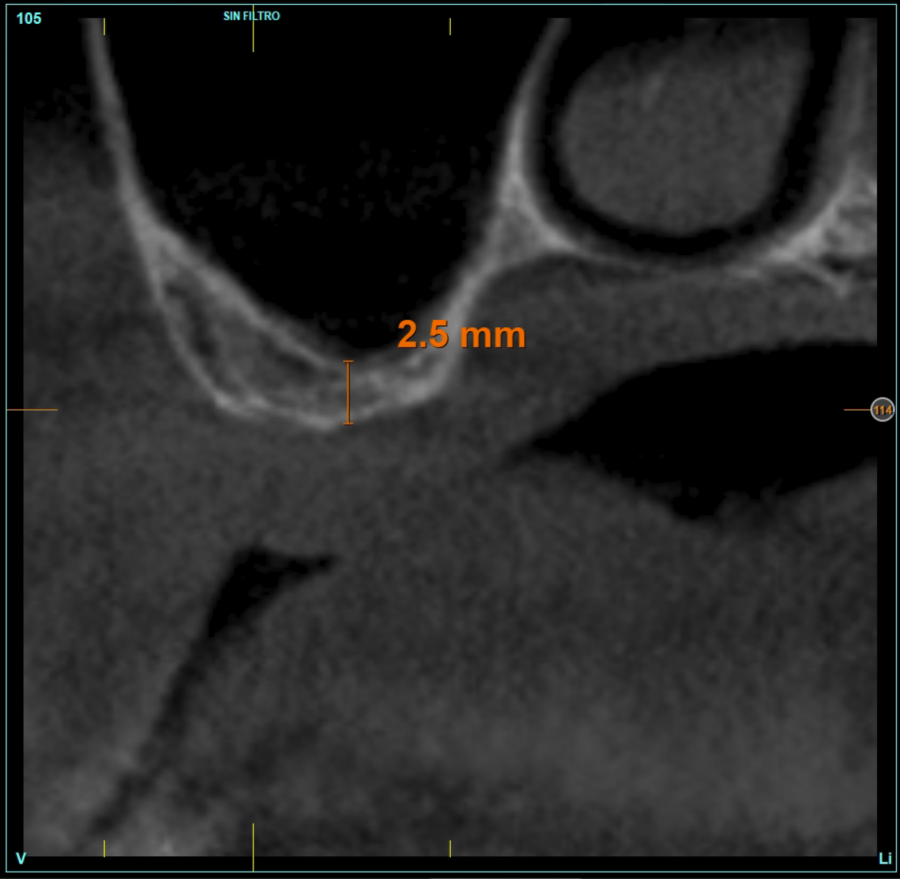

Material and method. A retrospective study has been carried out in patients in whom extra-short implants (4.5 and 5.5 mm length) were inserted directly by transcrestal elevation with residual ridges between 2 and 3 mm. The implant was the analysis unit for the descriptive statistics regarding location, implant dimensions, and radiographic measurements. The patient was the measurement unit for the analysis of age, sex and medical history. The main variable was the gain in height over the apex of the implant after 6 months of the surgery and one year after the load comparing both measurements and as secondary variables the biological complications and the implant failure were recorded.

Patients were retrospectively selected in which extra-short implants were inserted using the crestal lift technique using frontal drills, according to the technique used and described by our study group13, which surgery was carried out before 2015 to have a load follow-up period of at least 5 years, and in which the residual bone height was less than 3 mm.

In all cases, a diagnosis was made based on study models, intraoral examination of the patient and performing a Cone-beam analysed using the specific BTI-Scan 3 software (Biotechnology Institute, Vitoria, Alava, Spain).

Patients attend subsequent check-ups performing a control Cone-Beam after 5 months (before loading the implant) and after one year of the load, performing a new measurement in these images to analyse the bone gain and the maintenance of the same. In these check-ups, data are collected on prosthetic complications or crestal bone loss in these patients, as well as possible failures.

The mean height of the residual bone volume was 3.1 mm (+/- 0.3 mm with a range of 3-4 mm). In all cases, transcrestal sinus elevation was performed, with particulate autologous bone obtained from milling the neo alveolus generation zone for implant insertion, being the average of this elevation above the apex of the implant of 2.8 mm (+/- 0.99 range 1.9 -5 mm). In the CT control scan after one year of inserting the studied implants, the bone gain achieved was maintained, no decrease in the volume gained was observed, only three cases showed a decrease of between 0.4 and 0.5 mm of the initial volume at the end (Table).

Figures 2-19 show one of the cases included in the study.